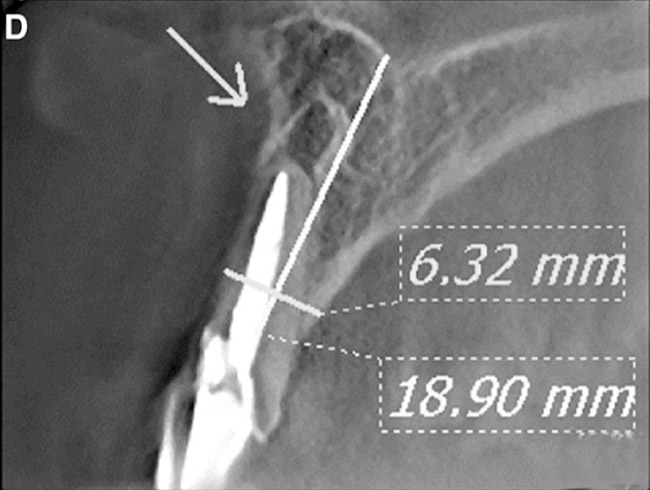

Figure 1d  Panoramic (A) and periapical radiographs (B, C) reveal the absence of periapical rarefaction in the area of the upper right central incisor. However, evidence of apical periodontitis can be seen clearly using the CBCT21 (D, E).

Figure 1d

Figure 1e  Panoramic (A) and periapical radiographs (B, C) reveal the absence of periapical rarefaction in the area of the upper right central incisor. However, evidence of apical periodontitis can be seen clearly using the CBCT21 (D, E).

Figure 1e

In addition to linear accuracy, it has been suggested that CBCT can have diagnostic accuracy with regards to periapical lesions.17-19 In one of these studies,17 periapical lesions were analyzed with CBCT, then surgically excised and biopsied to compare with histology. The authors found comparable results. Although the study showed promising results with CBCT, the researchers conceded that histology remains the gold standard in the diagnostic armamentarium. In another study,19 the ability to identify periapical lesions was assessed using radiographs and spiral CT. With CT, 100% of lesions were identified, while only 78% were identified with radiographs alone. Concomitantly, the location of the lesions proximal to the inferior alveolar nerve was visualized more readily with CT (100% vs 39%). Figure 1A through Figure 1E illustrate a case in which an endodontically treated tooth appeared normal on panoramic and periapical radiographs. Only CBCT showed the presence of apical pathology.6